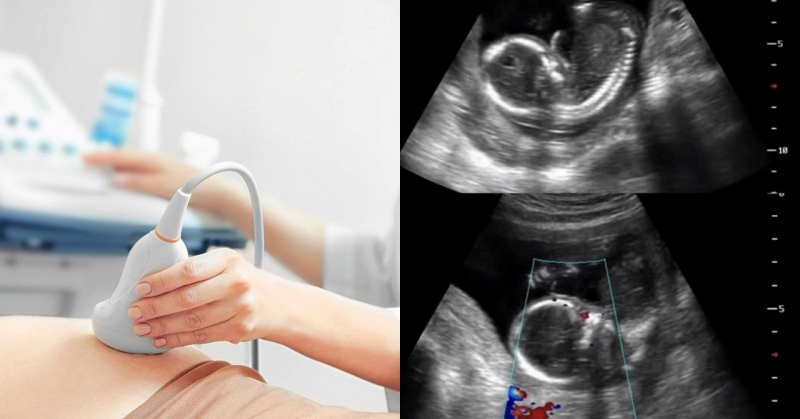

Một sản phụ mang thai 36 tuần vừa phải nhập viện cấp cứu và phẫu thuật lấy thai khẩn cấp do thai nhi đột ngột giảm cử động sau khi người mẹ ăn thực phẩm bảo quản không đúng cách trong tủ lạnh.

Theo truyền thông Trung Quốc, sau khi đánh giá toàn diện, các bác sĩ nghi ngờ thai nhi bị suy hô hấp cấp tính. Để đảm bảo an toàn cho cả mẹ và bé, đội ngũ sản khoa ngay lập tức quyết định thực hiện phẫu thuật mổ lấy thai khẩn cấp.

Sau khi nhận được thông báo, các bác sĩ đã đến phòng mổ sớm, chuẩn bị dụng cụ hồi sức và trong tình trạng cảnh giác cao độ. Em bé sơ sinh được sinh ra trong tiếng khóc rõ ràng, không bị ngạt thở, nhưng khi khám thì thấy có phát ban rải rác khắp cơ thể. Khoảng 15 phút sau, em bé bắt đầu khó thở và được chuyển ngay đến phòng chăm sóc đặc biệt sơ sinh để hỗ trợ thở máy. Các xét nghiệm cho thấy nồng độ protein phản ứng C (CRP) tăng cao đáng kể, cho thấy nhiễm trùng nặng.

Trong quá trình hỏi thêm về tiền sử bệnh của bệnh nhân, một manh mối quan trọng đã xuất hiện: người mẹ đã ăn thức ăn thừa được bảo quản trong tủ lạnh trong vòng hai ngày trước đó và bị sốt trước khi sinh. Dựa trên biểu hiện lâm sàng và tiền sử dịch tễ học, nhóm bác sĩ nghi ngờ người phụ nữ nhiễm khuẩn Listeria, kết quả cấy máu sau đó xác nhận dương tính với Listeria monocytogenes.